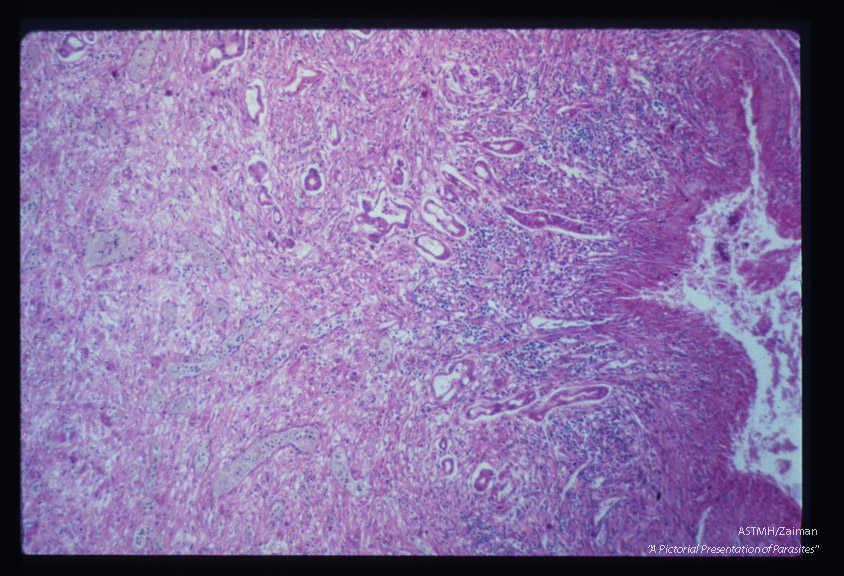

Wall of liver abscess.

Entamoeba histolytica

Description: Wall of liver abscess.